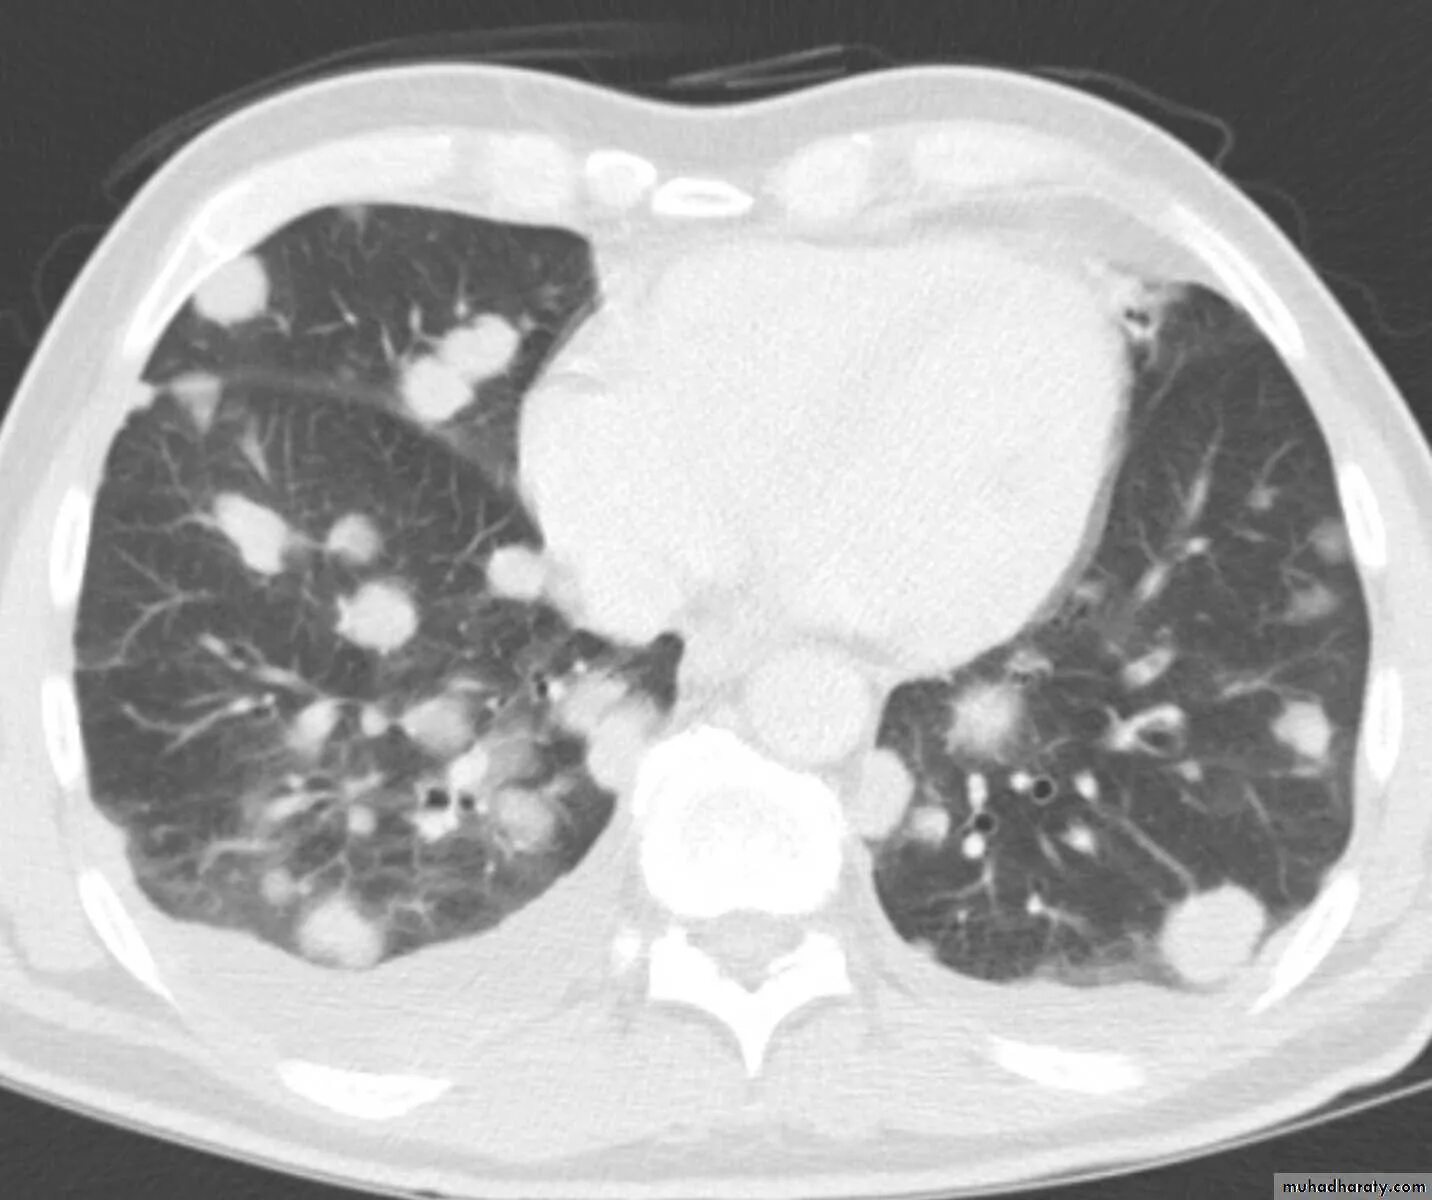

Метастазы щитовидной железы в легкие